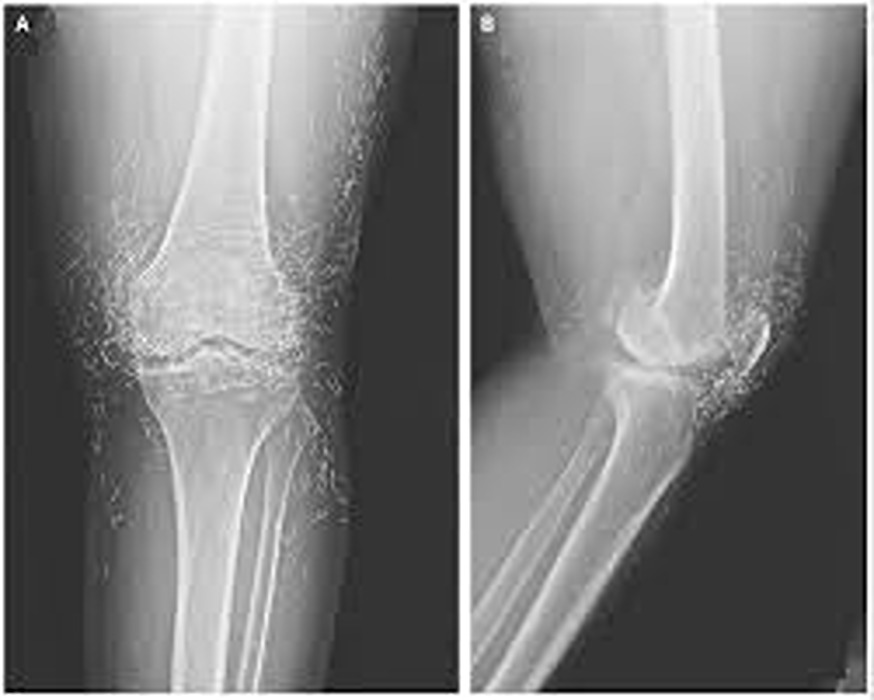

What started as a routine hospital visit for knee pain turned into a medical mystery that left doctors speechless. A 65-year-old woman in South Korea went in expecting a diagnosis of arthritis — but when her X-ray appeared on the screen, the room fell silent. Her knee joint wasn’t just worn down from age; it was filled with dozens of tiny gold needles. The strange discovery sparked immediate questions about how they got there and why they had remained unnoticed for so long.

Doctors soon learned that the woman had been struggling with osteoarthritis for years, a condition that makes everyday movement painful as cartilage breaks down. Frustrated by the limits of conventional medicine, she had turned to acupuncture — a centuries-old therapy believed to ease pain and improve circulation. But instead of using temporary needles, her acupuncturist had inserted fine gold ones beneath the skin permanently, convinced they would provide lasting healing energy.

The shocking X-ray served as a cautionary reminder of how alternative treatments can sometimes go too far. Specialists warn that leaving any metal object inside the body can cause inflammation, infection, and complications during imaging procedures. While acupuncture, when performed properly, is generally considered safe, experts emphasize that permanent implants are not medically approved or supported by evidence.